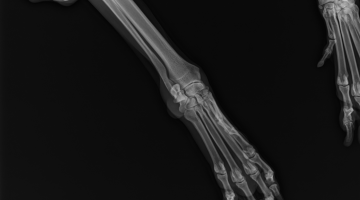

Attualmente la nostra struttura è munita di un apparecchio radiologico digitale indiretto Fuji. (Nella photogallery in basso). I vantaggi di questa tecnologia rispetto alla radiologia “analogica “ tradizionale sono molteplici. Primo fra tutti la qualità dell’immagine e la possibilità di ingrandire i particolari, correggere i contrasti, visualizzarla in negativo, ma anche misurare con precisione i dettagli. Poi la notevole riduzione dei tempi dello studio radiografico che in campo veterinario significa anche la riduzione dei tempi di anestesia del paziente con beneficio per la sua salute. Le lastre digitali non inquinano l’ambiente. Sono dei files che possono essere trasmessi per posta elettronica, masterizzati su cd o pennette di memoria da mettere nella cartella clinica da consegnare al proprietario del paziente e, nel caso della nostra struttura allegati in rete e nella scheda clinica dell’animale.